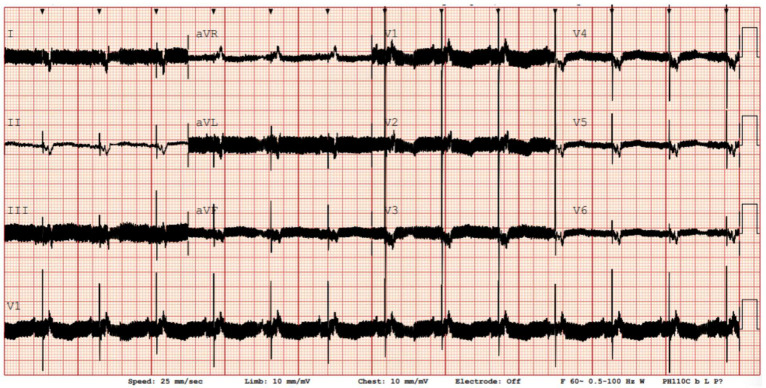

室性心律失常(VAs)是左心室辅助装置(lvad)支持患者常见且临床上重要的并发症,在植入后的第一年发生的病例高达50%。尽管lvad提供了血液动力学支持,但VAs与发病率和死亡率增加有关,主要是通过反复的植入式心律转复除颤器(ICD)休克和右心室衰竭。在这一人群中,VAs的潜在机制是多因素的,包括结构性心肌重构、器械相关因素和预先存在的心律失常底物。当抗心律失常药物治疗和设备重编程不足时,导管消融已成为一种有价值的治疗选择,尽管手术时机(植入前、植入内或植入后)和方法仍在讨论中。LVAD手术期间的心外膜通路可能为特定患者提供优势,而植入后的消融由于解剖结构改变和电磁干扰而带来技术挑战。本文综述了LVAD受者的流行病学、病理生理学、风险分层和VAs管理,强调了导管消融的技术考虑、程序安全性和临床结果。多学科方法在指导个性化治疗和优化这一复杂人群的结果方面仍然至关重要。正在进行的研究将为心律失常的最佳管理提供更多的见解,特别是关于导管消融的最佳时机。新技术的影响,如无创测绘和手术前成像,也需要进一步评估。

Ventricular arrhythmias (VAs) are common and clinically important complications in patients supported by left ventricular assist devices (LVADs), occurring in up to 50% of cases within the first year after implantation. Despite the hemodynamic support provided by LVADs, VAs are linked to increased morbidity and mortality, primarily through recurrent implantable cardioverter defibrillator (ICD) shocks and right ventricular failure. The underlying mechanisms of VAs in this population are multifactorial, involving structural myocardial remodeling, device-related factors, and pre-existing arrhythmic substrates. Catheter ablation has become a valuable treatment option when antiarrhythmic drug therapy and device reprogramming are inadequate, though procedural timing (pre-, intra-, or post-implantation) and approaches remain under discussion. Epicardial access during LVAD surgery may provide advantages for selected patients, while ablation after implantation poses technical challenges due to altered anatomy and electromagnetic interference. This review offers a comprehensive overview of the epidemiology, pathophysiology, risk stratification, and management of VAs in LVAD recipients, emphasizing technical considerations, procedural safety, and clinical outcomes of catheter ablation. A multidisciplinary approach remains essential in guiding personalized treatment and optimizing outcomes for this complex population. Undergoing studies will provide more insight into optimal management of arrhythmias, particularly regarding the optimal timing of catheter ablation. The impact of new technologies such as non-invasive mapping alongside pre-procedural imaging needs also to be further evaluated.